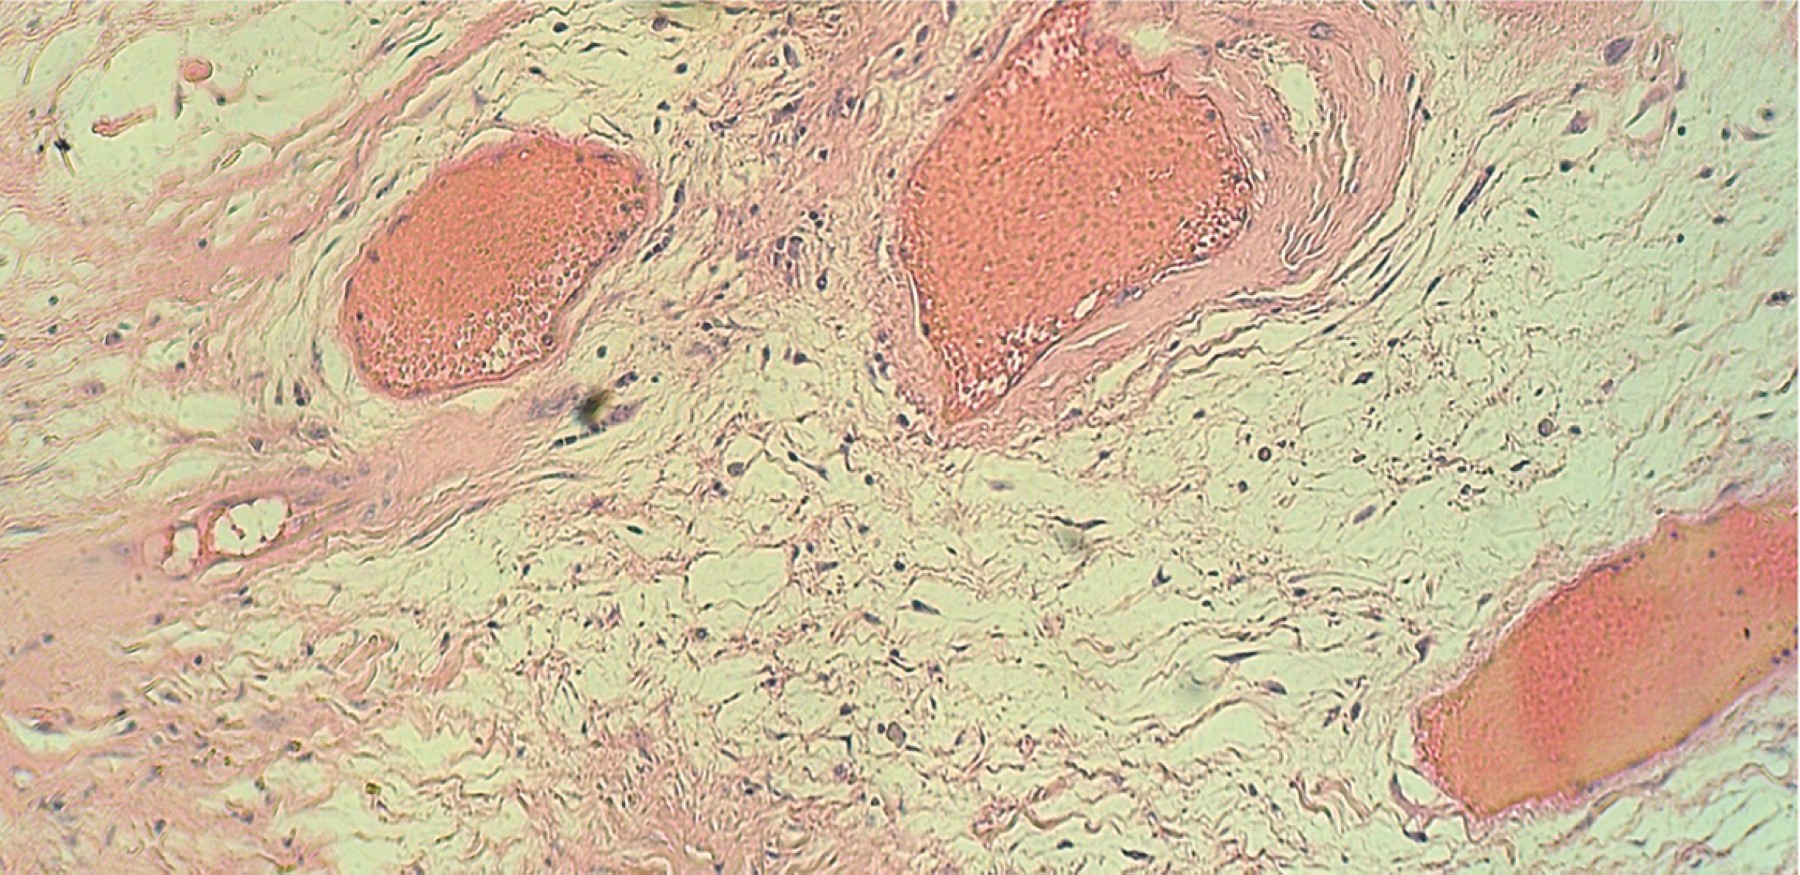

Figure 2